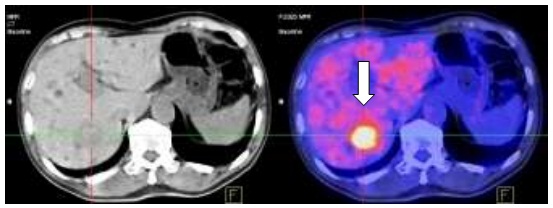

Hình 1.3. Nốt di căn phổi kích thước: 0,5cm, SUV=1,6.

Hình 2.4. Trước điều trị: Nốt mờ phổi phải

Hình 2.5. Sau điều trị: không thấy nốt mờ phổi